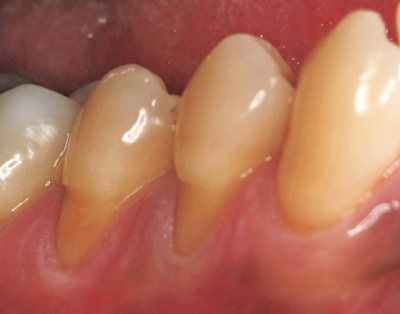

40歳の男性。下顎右側小臼歯部の冷水痛を主訴として来院した。初診時の口腔内写真を別に示す。

考えられる原因はどれか。2つ選べ。

a. 摩耗

b. 歯頸部齲蝕

c. ブラキシズム

d. 歯の外部吸収

e. エナメル質形成不全